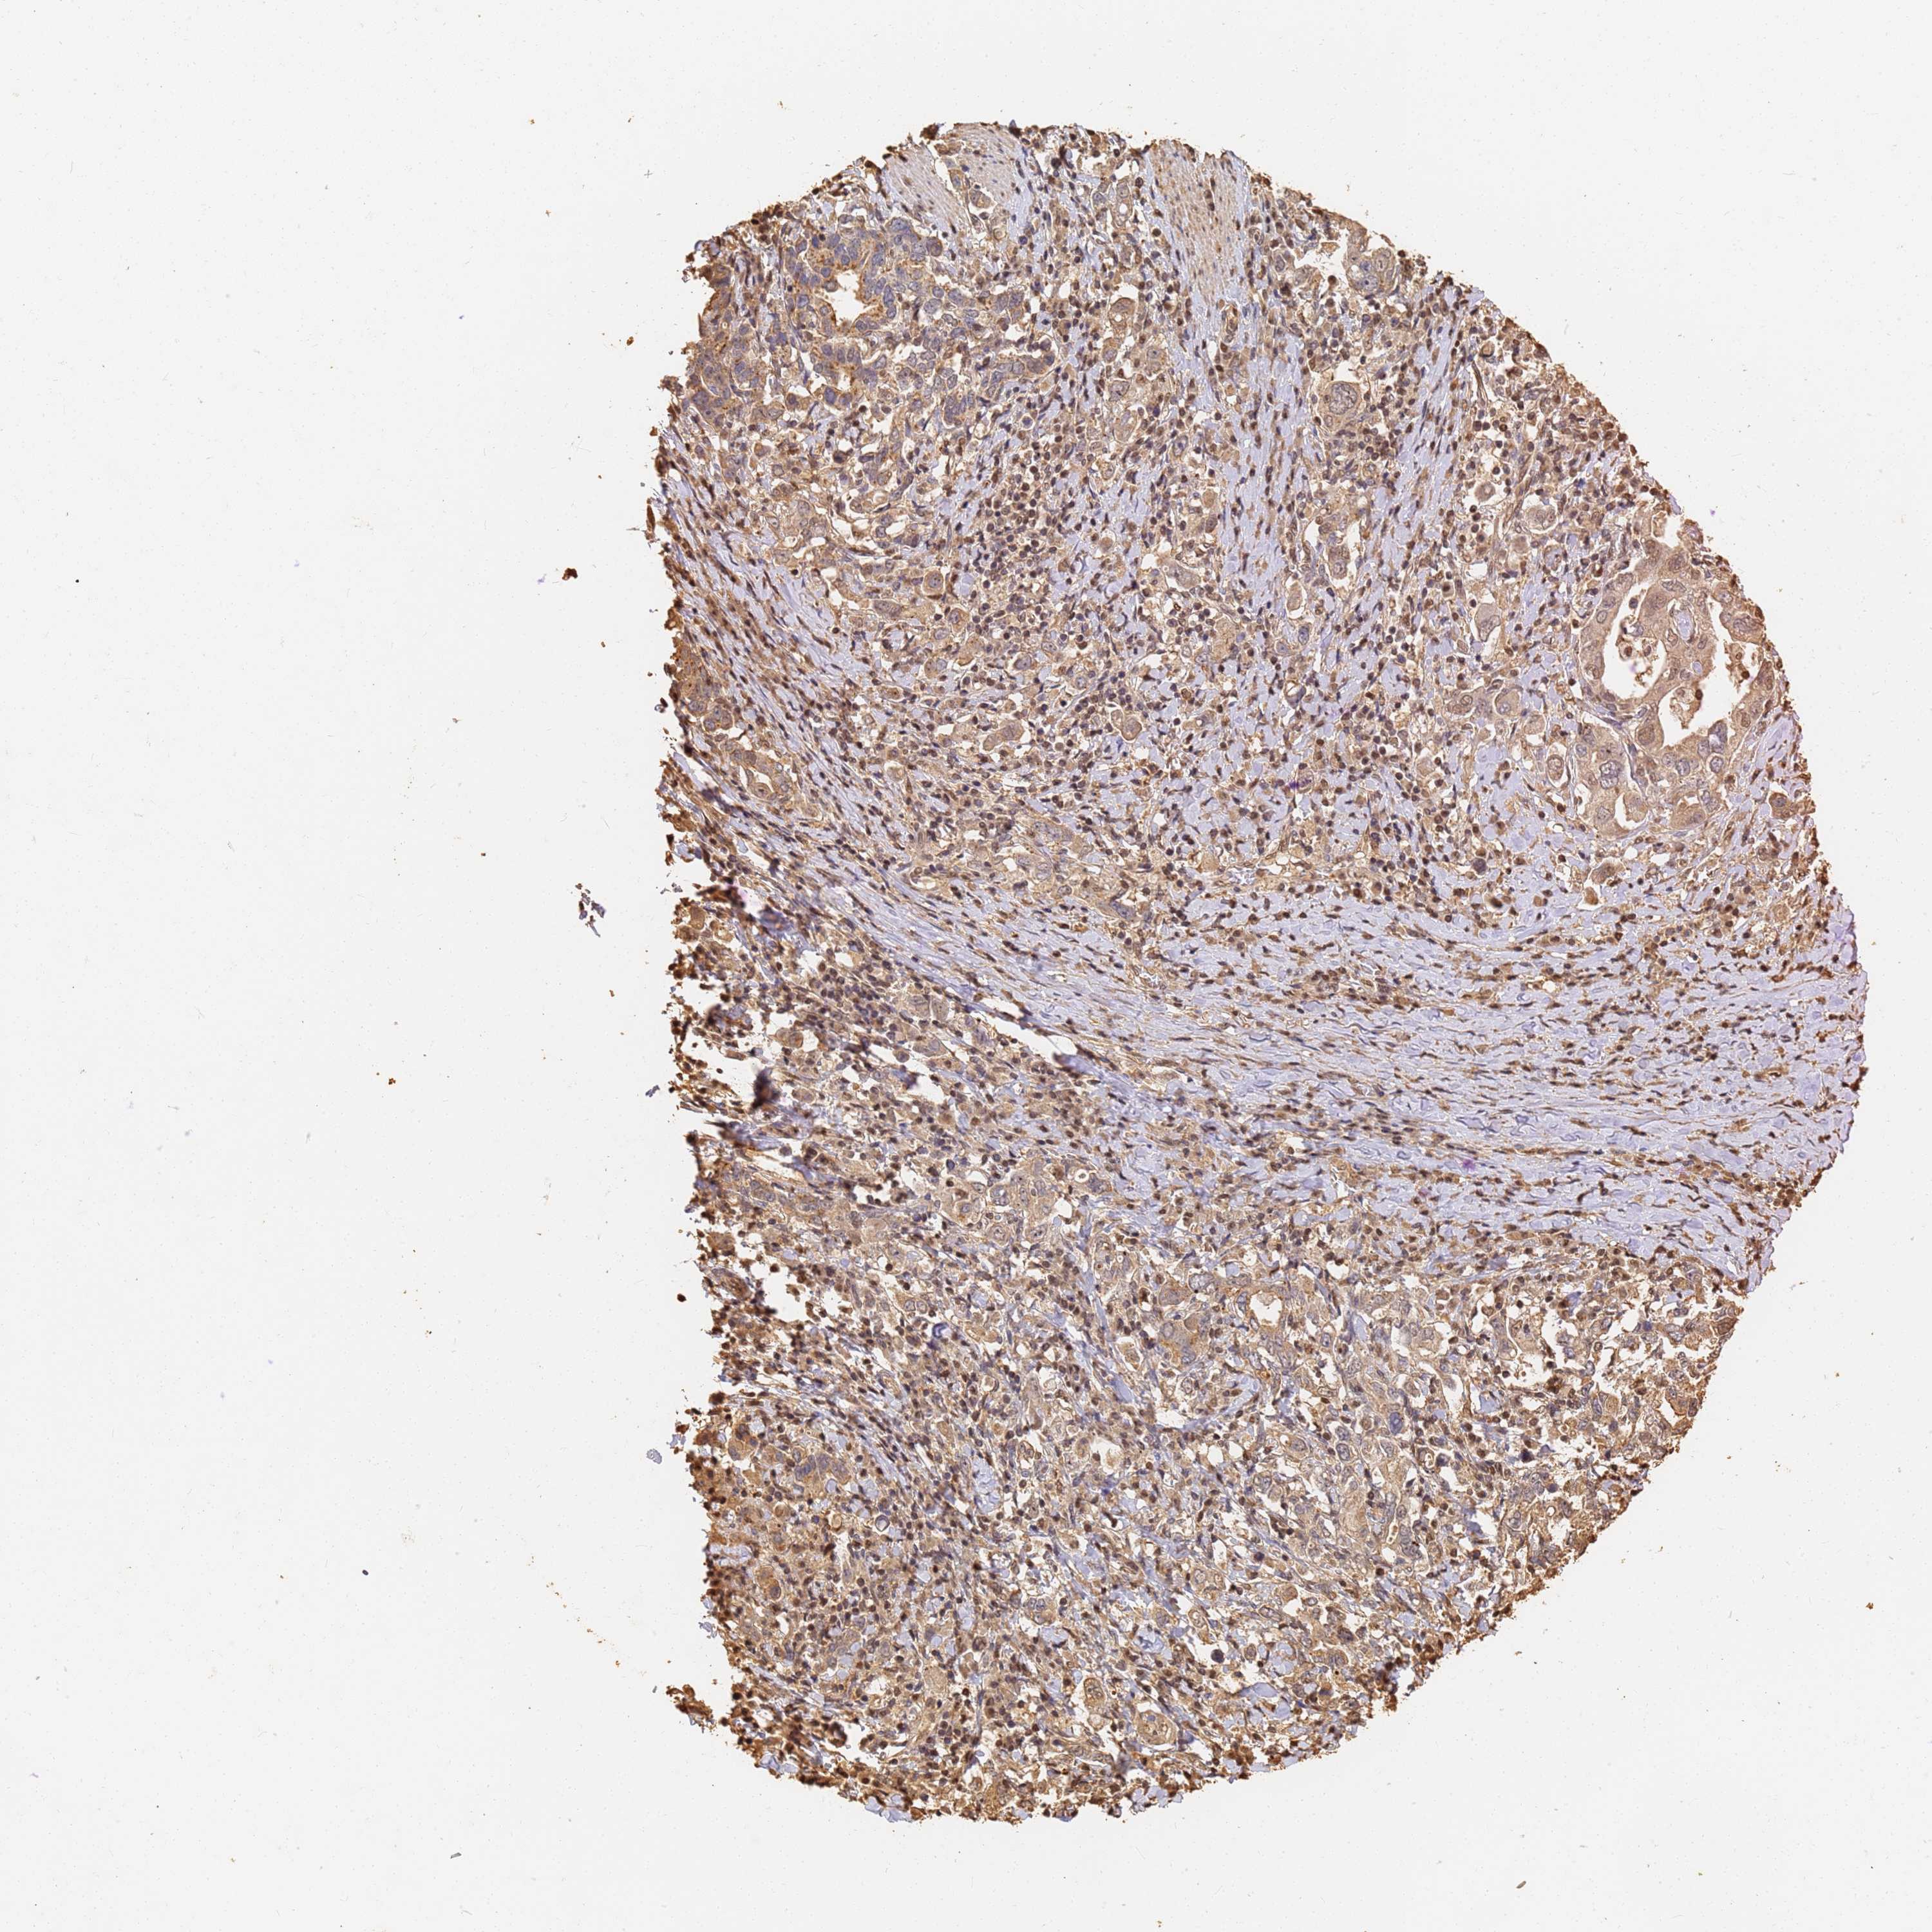

STOMACH CANCER - Protein expressioni

A mouse-over function shows sample information and annotation data. Click on an image to view it in a full screen mode. Samples can be filtered based on level of antibody staining by selecting one or several of the following categories: high, medium, low and not detected. The assay and annotation is described here.

Note that samples used for immunohistochemistry by the Human Protein Atlas do not correspond to samples in the TCGA dataset.

Antibody stainingi

Antibody staining in the annotated cell types in the current human tissue is reported as not detected, low, medium, or high, based on conventional immunohistochemistry profiling in selected tissues. This score is based on the combination of the staining intensity and fraction of stained cells.

Each image is clickable and will lead to virtual microscopy that enables deeper exploration of all samples and also displays staining intensity scores, fraction scores and subcellular localization as well as patient and tissue information for each sample.

Antibody HPA040820

Antibody CAB013089

Staining

High

Medium

Low

Not detected

Intensity

Strong

Moderate

Weak

Negative

Quantity

>75%

75%-25%

<25%

None

Location

Nuclear

Cytoplasmic/membranous

Cytoplasmic/membranous,nuclear

Adenocarcinoma, NOS